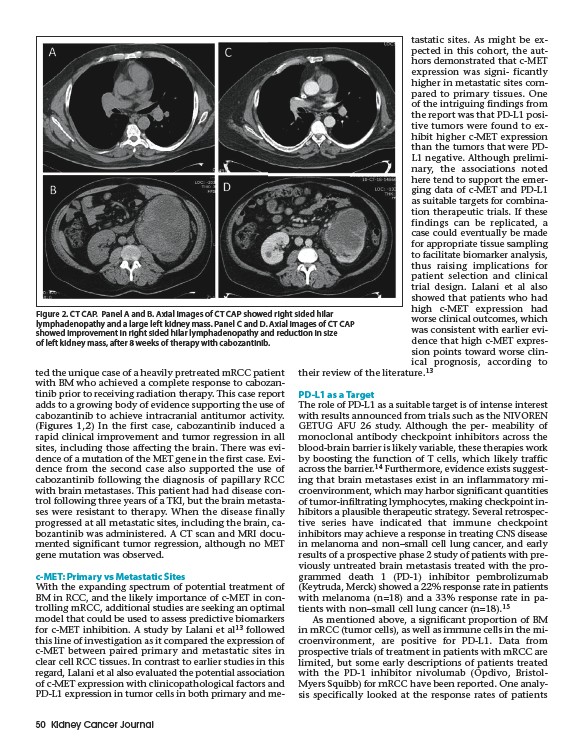

Figure 2. CT CAP. Panel A and B. Axial images of CT CAP showed right sided hilar

lymphadenopathy and a large left kidney mass. Panel C and D. Axial images of CT CAP

showed improvement in right sided hilar lymphadenopathy and reduction in size

of left kidney mass, after 8 weeks of therapy with cabozantinib.

(Figures 1,2) In the first case, cabozantinib induced a

rapid clinical improvement and tumor regression in all

sites, including those affecting the brain. There was evidence